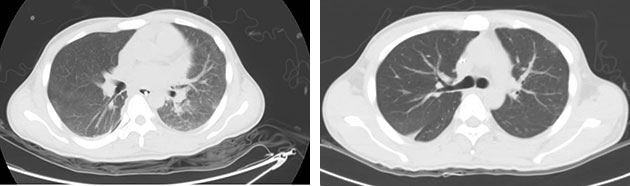

江稳强主任立即带领EICU医护人员床边查看和组织抢救,迅速气管插管行有创机械通气,血氧饱和度有所回升,但患者呼吸窘迫仍持续不缓解,复查CT提示肺部渗出较之前一日明显增多,呈“大白肺”表现,患者生命垂危。

患者CT影像显示肺部渗出严重,呈“大白肺”

病因既明,当机立断,立即在强有力的呼吸功能支持下,同时给予大剂量激素和静脉丙种球蛋白冲击治疗。经过三天的冲击治疗,患者感染指标明显下降,双肺呼吸啰音无明显干湿啰音,体温降至正常,复查CT见渗出液明显吸收减少,也证明了李欣副院长对于病情的判断非常精准及时。在江稳强主任的指导下,根据病情实时调整患者的治疗方案,并于10月31日成功脱机拔管,改为鼻导管给氧,患者生命体征、精神状态、精神、睡眠恢复良好,住院治疗8天后康复出院。

对因治疗后,患者肺部病灶逐渐吸收减少